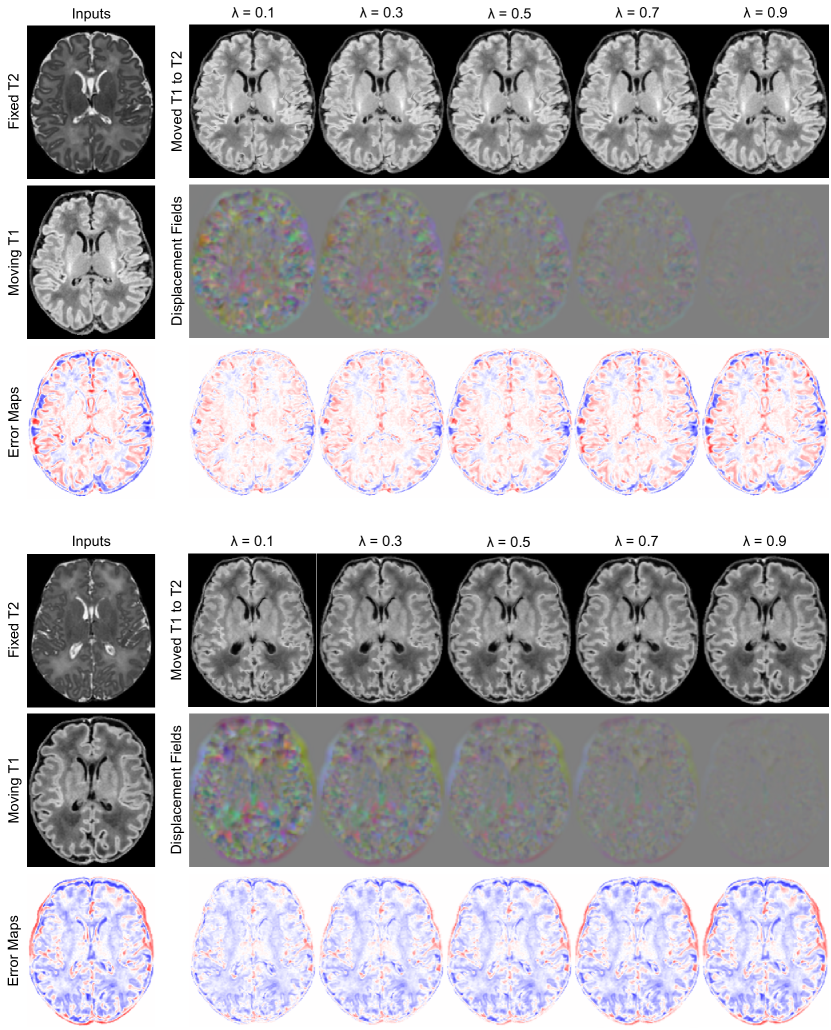

Refer to caption

Figure 2: T1w-T2w registration visualization between arbitrarily selected subjects for the (top) ch=64 and (bottom) ch=256 models. Error maps computed w.r.t. the T2w MRI of the target subject. Hypernetwork registration models are sampled with the same λ𝜆\lambda as Table 1.

Results. Sample registration visualizations are provided in Fig. 2, performance scores versus λ𝜆\lambda are plotted in Fig. 3, and a study of trading-off registration accuracy for smoothness is tabulated in Table 1. We make the following experimental observations: